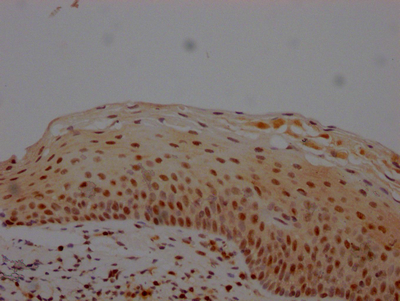

IHC image of CSB-RA966553A0HU diluted at 1:100 and staining in paraffin-embedded human tonsil tissue performed on a Leica BondTM system. After dewaxing and hydration, antigen retrieval was mediated by high pressure in a citrate buffer (pH 6.0). Section was blocked with 10% normal goat serum 30min at RT. Then primary antibody (1% BSA) was incubated at 4℃ overnight. The primary is detected by a Goat anti-rabbit IgG polymer labeled by HRP and visualized using 0.05% DAB.